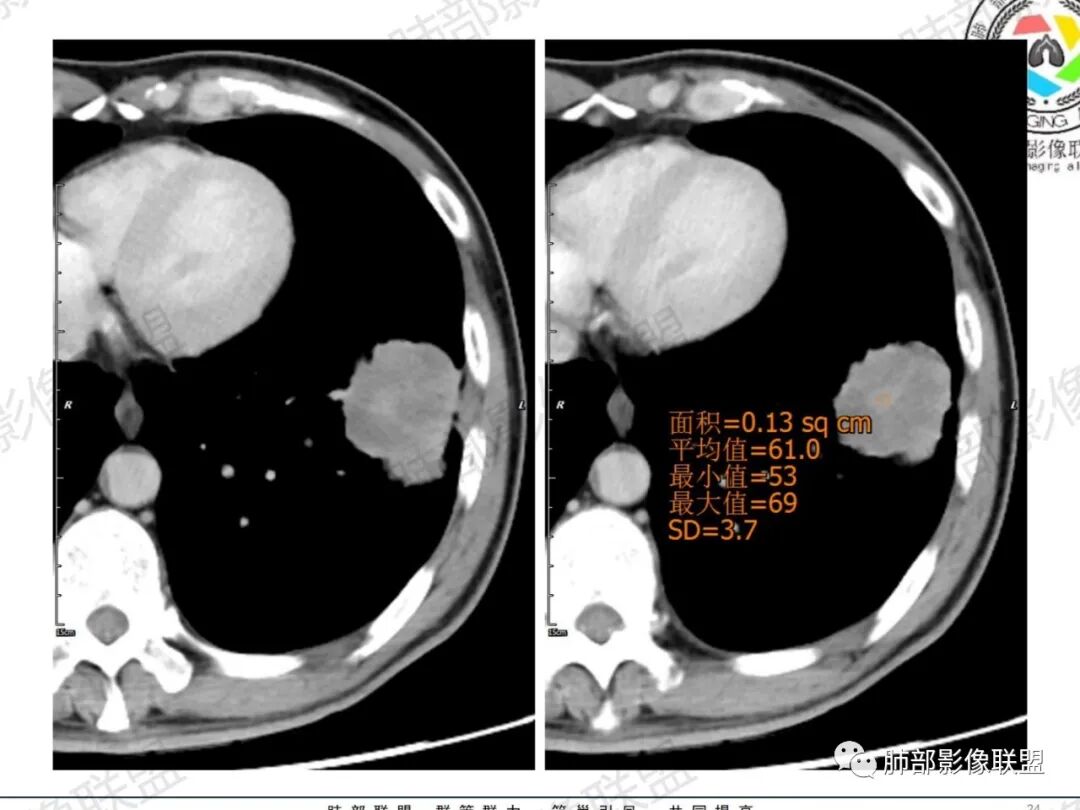

一切∮随缘:左肺下叶不规则肿块,边缘光滑,平直,局部彭隆,分叶,近端支气管堵塞,远端与胸膜相贴,平扫密度尚均匀,增强后不均匀强化,内部可见低密度坏死,胸膜下多发肺气肿,伴双肺散在光滑小结节,实验室肿瘤标志物高,考虑恶性:神经内分泌癌(大细胞),腺癌,鳞癌。

琦遇:恶性没有问题,肺气肿底子、病灶分叶、少许毛刺、叶间胸膜凹陷、部分边缘可见清晰的GGO、胸膜牵拉凹陷、局部胸水、近端支气管截断、部分支气管被推移、占位效应明显、强化特点为不均匀强化、内部有少许沼泽样低强化区,强化部分轻中强化为主、余肺可见转移性结节、左肺上叶似为囊腔型腺癌一枚,肿瘤标志物提示非小、神经内分泌,综合分析考虑大神泌、腺癌、腺鳞癌、鳞癌  同时左肺上叶囊腔型腺癌  肺转移

傅昌瑜:中老年男性,肺气肿背景,右胸背疼痛1周。CEA、NSE、CYFRA—211升高。左上肺混合磨玻璃结节,内见较多空泡和扩张支气管。左下肺胸膜下肿块,边缘较光滑,深分叶,似有血管进入,与支气管关系不清,内见不均匀强化,见沼泽地样坏死,有胸膜栽赃。另两肺多发圆形小结节。考虑恶性并肺内转移,多原发可能性大,左上肺腺癌,左下肺病理难以判断,小细胞癌?鳞癌?

LCNEC最常见的影像特征包括:(1)肿块发生部位:周围型肺癌为主,少数发生于肺中央。(2)肿块大小及形态。因肿瘤细胞生长迅速常形成较大肿块,因此其体积一般较大,直径常在3~10cm范围内,病灶常为不规则形软组织肿块。(3)肿块边界。多数学者报道大多数肿块边界清晰,边缘呈分叶状,毛刺征及“胸膜凹陷征”少见,认为与该病对周围组织浸润较轻及较少产生纤维瘢痕组织牵拉有关联。(4)肿块密度、强化特点及代谢情况。据文献报道,该类肿瘤因体积较大CT上常见软组织肿块,且多数密度不均匀,内见囊变坏死区,增强后呈轻或中度不均匀强化(可见强化者占75.7%),认为其强化特点与其内部肉眼可见坏死灶和肿瘤较大直径有关。(5)伴随症状及远处转移。该病恶性程度高,侵袭性强,常侵犯邻近结构,如胸膜、心包、邻近骨质或纵隔内组织等,易出现纵隔淋巴结转移,部分发生肺内及远处转移,少数早期可出现广泛远处转移。